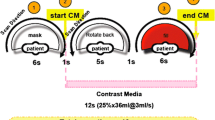

All interventions were performed using a robotic angiographic suite (Artis Zeego Q, VE 40 A, Siemens, Forchheim, Germany). For acquisition of PBV maps, an unenhanced rotation (mask run) and contrast enhanced rotations (return and fill run) were acquired (Acquisition time per rotation 4 s, total examination time 16 s, 90 KV, 200 ° total angle, 0.8° per frame, 248 frames, matrix 616x480 pixel, flat panel pixel size 616 μm, dose 0.36μGy per frame). For the contrast enhanced rotation, a total of 30 ml diluted contrast media [7,5 ml Ultravist 370 (Bayer Schering, Leverkusen, Germany) and 22,5 ml saline solution] was injected by an automated power injector (Accutron-HP-D, Medtron, Saarbrücken, Germany) with a flow rate 3 ml/s. Contrast injection was manually triggered after mask run, to guarantee a contrast enhanced acquisition in a steady state of liver perfusion, according to a previous study on PBV of the liver [16]. As blood volume refers to the amount of blood which is present at a given moment, it can be assumed to be constant during the time of acquisition. This makes the calculation of CBV from only two measurements possible: a base-line (mask) acquired before contrast administration and the contrast distribution (fill) after contrast injection. Acquired data allowed reconstruction of non-enhanced images, contrast enhanced images (arterial phase) including tumour feeding vessels, and PBV maps.